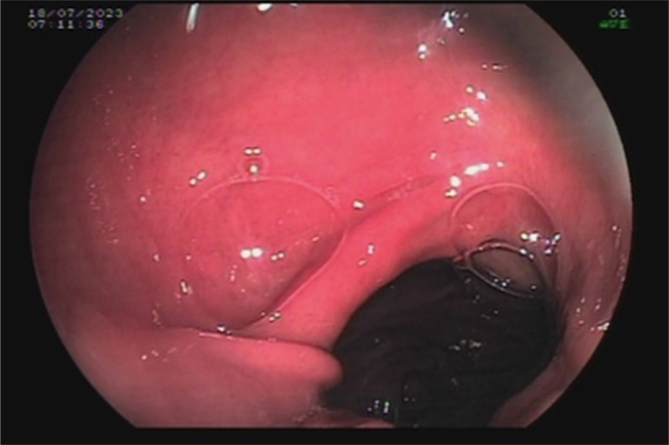

HETEROTOPIC GASTRIC MUCOSA OF THE ESOPHAGUS AS A POTENTIAL CAUSE OF PEPTIC STENOSIS AFTER ROUX-EN-Y GASTRIC BYPASS.

{"title":"HETEROTOPIC GASTRIC MUCOSA OF THE ESOPHAGUS AS A POTENTIAL CAUSE OF PEPTIC STENOSIS AFTER ROUX-EN-Y GASTRIC BYPASS.","authors":"João Victor Vecchi Ferri, Wagner Herbert Sobottka, José Alfredo Sadowski, Gustavo Rodrigues Alves Castro, Vitor Mamoru Haida, Marcela Scardua Cocicov, João Caetano Dallegrave Marchesini","doi":"10.1590/0102-6720202400055e1849","DOIUrl":null,"url":null,"abstract":"","PeriodicalId":72298,"journal":{"name":"Arquivos brasileiros de cirurgia digestiva : ABCD = Brazilian archives of digestive surgery","volume":"37 ","pages":"e1849"},"PeriodicalIF":1.8000,"publicationDate":"2025-01-20","publicationTypes":"Journal Article","fieldsOfStudy":null,"isOpenAccess":false,"openAccessPdf":"https://www.ncbi.nlm.nih.gov/pmc/articles/PMC11745473/pdf/","citationCount":"0","resultStr":null,"platform":"Semanticscholar","paperid":null,"PeriodicalName":"Arquivos brasileiros de cirurgia digestiva : ABCD = Brazilian archives of digestive surgery","FirstCategoryId":"1085","ListUrlMain":"https://doi.org/10.1590/0102-6720202400055e1849","RegionNum":0,"RegionCategory":null,"ArticlePicture":[],"TitleCN":null,"AbstractTextCN":null,"PMCID":null,"EPubDate":"2025/1/1 0:00:00","PubModel":"eCollection","JCR":"","JCRName":"","Score":null,"Total":0}